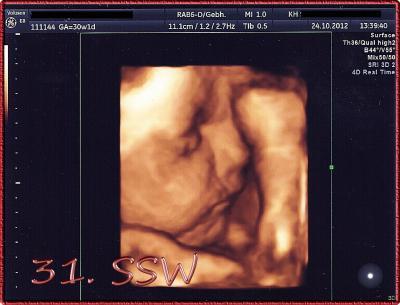

Hallo Ihr Lieben, nun endlich hab ich Zeit gefunden, um Euch von meinen Arztbesuchen heute zu berichten. Heute früh war ich bei meiner Gynäkologin, es gab ein CTG - alles perfekt. Obwohl die Maus ziemlich aktiv war - sie wollte sich immer verstecken, geht aber nun nicht mehr - konnten wir ein schönes CTG schreiben. Alles perfekt. Mein Muttermund ist stabil und fest verschlossen, der Gebärmutterhals ist lang genug (genaue Länge hat sie mir nicht genannt) und der Beckeneingang noch völlig frei. Mein harter Bauch und der Druck nach unten sind also definitiv KEINE "echten" Wehen, sondern nur Übungskontraktionen. *freu* Dann hatte ich ja mittags den Doppler-US im KH. Auch dort wurde noch einmal CTG geschrieben, ist so üblich dort. Auch dieses CTG war super, wir bekommen ein sehr aktives Kind - Aussage des Chefarztes. Beim Doppler ist auch alles völlig okay, der erhöhte Widerstand in der einen Uterusaterie ist völlig verschwunden *doppelfreu* und ich muss mir keine Gedanken machen. Die Kleine war heute auch seeeehr kooperativ, sie hat den US komplett verschlafen. Der Arzt konnte also in aller Ruhe ausmessen und wir haben endlich genaue Masse (sofern man einen US als genau bezeichnen kann ;) ) ... Meine Gynäkologin hatte sich wohl vor zwei Wochen bei der FL ziemlich vermessen (kann bei einem Zappelkind schon mal vorkommen). Heute ergab der US folgende Masse: 41 cm gross 1861 g schwer Kopfumfang 28,35 cm Bauchumfang 29,21 cm FL 5,75 cm BPD 7,73 cm FOD 10,32 cm Meine kleine Polter-Elfriede ist völlig zeitgerecht entwickelt - nicht zu gross und auch nicht zu schwer - und das trotz meines GDM. Ich bin soooooo erleichtert. Es sieht alles völlig normal aus. Nur das Fruchtwasser ist an der oberen Grenze, aber eben noch immer in der Norm. Was will ich mehr???? Und als krönenden Abschluss gabs ein tolles Bild dazu ♥ ♥ ♥

Bild zu Ergebnisse VU und Doppler-US mit Foto :) - Forum für Januar - Mamis

TOLL!!! Freue mich für dich, dass alles so toll gelaufen ist, Mutter und Kind wohlauf sind und alles gut verläuft!! Das Bild ist megasüß, muss auch dringend mal meine 3D-Pics von unserer Kröte einscannen. :D

Echt total schön! Auch das Bild!! Und wenn man sich die Daten so vor Augen hält, wie gross sie schon ist, dann wird einem nochmal bewusst, dass es ja auch nicht mehr lange hin ist bis unsere Mäuse auf die Welt kommen!!! Hihi!

Hallo Murmel (welch passender Nick übrigens für unseren Zustand ) meine Maus liegt mit ihrem Gewicht fast auf der 95. Perzentile, was heisst, dass sie schon etwas schwerer ist als der Durchschnitt, aber eben nicht ZU schwer Es kann schon sein, dass Deine Maus ca. 1300 g wiegt, dann ist sie einfach etwas zarter. Warte mal ab, die Kleinen nehmen jetzt rasant an Gewicht zu. Der Arzt meinte gestern, dass wir schon die 4 kg-Marke erreichen und bestimmt sogar knacken werden Das Bild ist echt der Hammer, ich bin sooooo glücklich, dass wir dieses Mal so ein tolles Bild bekommen haben. Könnte es stundenlang angucken und hab es mir schon als Hintergrund im Handy eingestellt Vielleicht bekommst Du nächste Woche auch so ein tolles Bildchen, wer weiss ??? LG Snow